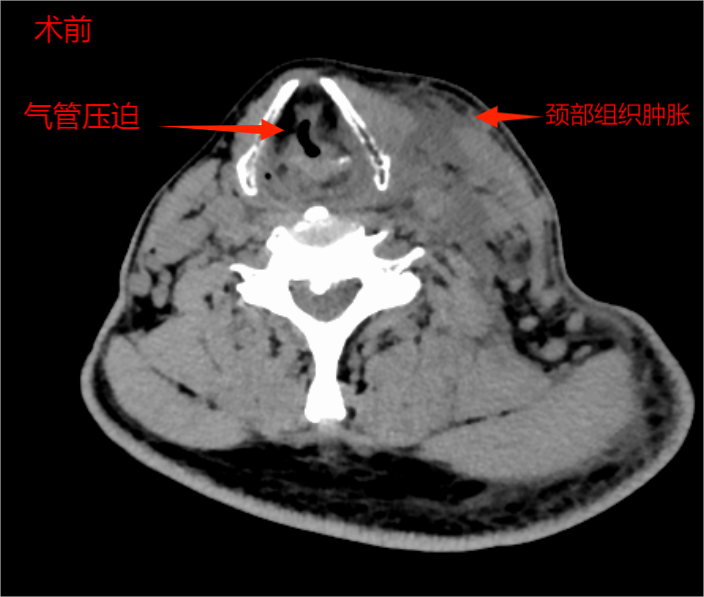

经过多科精心治疗与严密监测,患者感染得到控制,呼吸功能显著改善,复查CT颈部肿胀较前消退,气道压迫表现较前明显缓解,达到安全拔除气管插管的标准。当李伯成功脱离呼吸机,恢复自主呼吸的那一刻,标志着治疗取得了阶段性重大胜利。拔管第二天,李伯在呼吸与危重症医学科主管医师周世全和康复科治疗师莫兆财专业指导下便可在床旁活动。这不仅同步指导患者进行基础呼吸功能训练,还可以加速呼吸功能恢复,循环地进行了体能训练。

术前术后对比